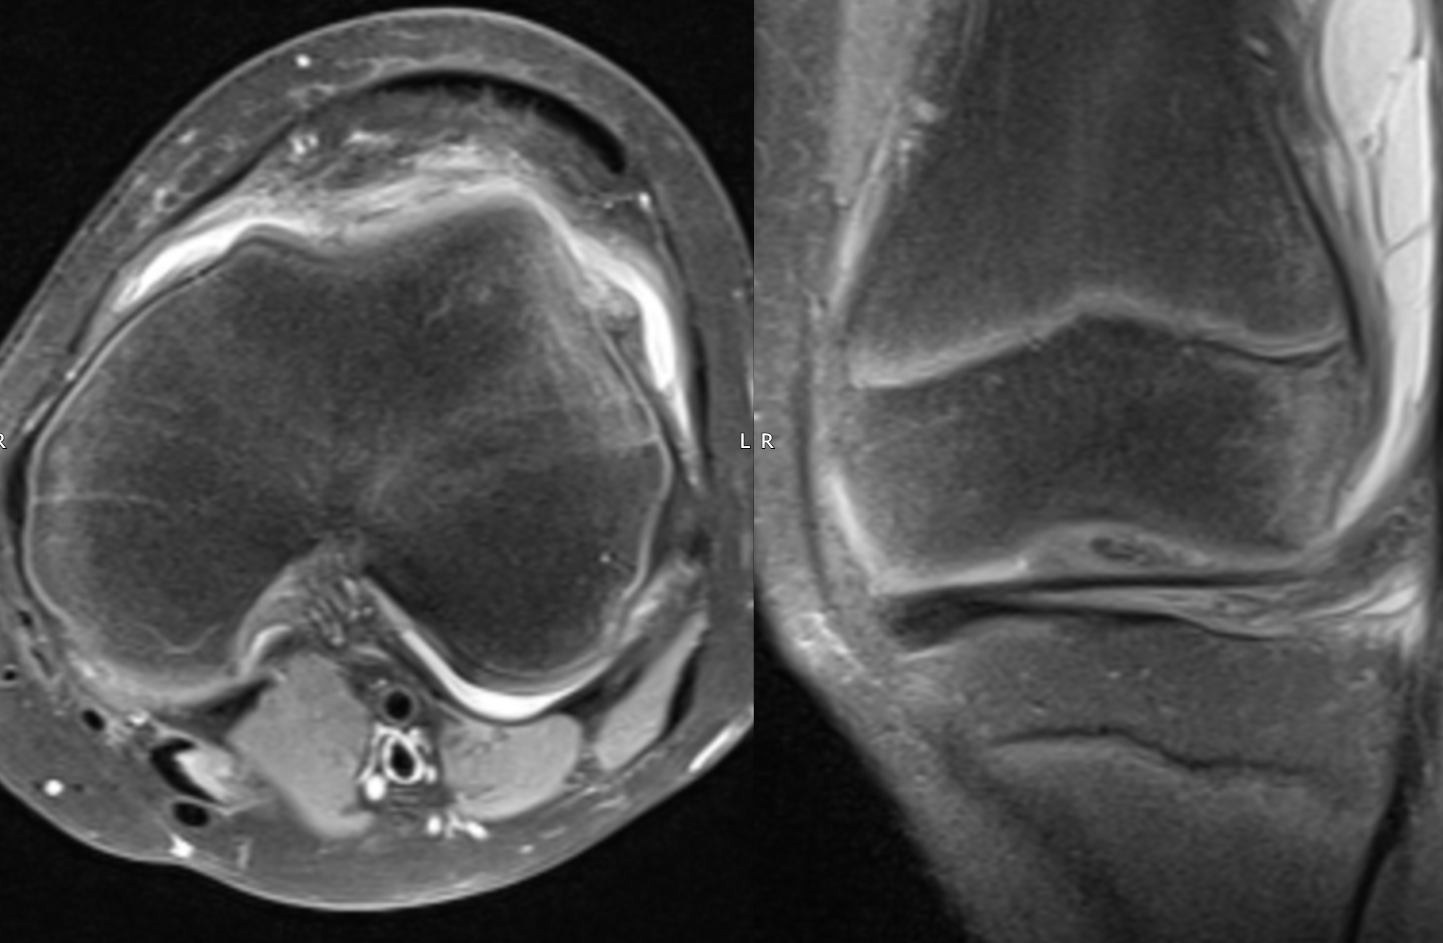

Another case of transient patellar dislocation:

20 y woman.

PD FS Axi & Cor: Bone marrow oedema of the inferomedial aspect of the patella and lateral aspect of the lateral femoral condyle is noted in keeping with contusion due to transient patellar dislocation. There is a tear of the anterior aspect of the medial patellofemoral ligament (MPFL). Small amount of effusion can be traced along the fibres of the swollen MPFL. Minor bone marrow oedema is also noted at the site of the femoral insertion of MPFL.